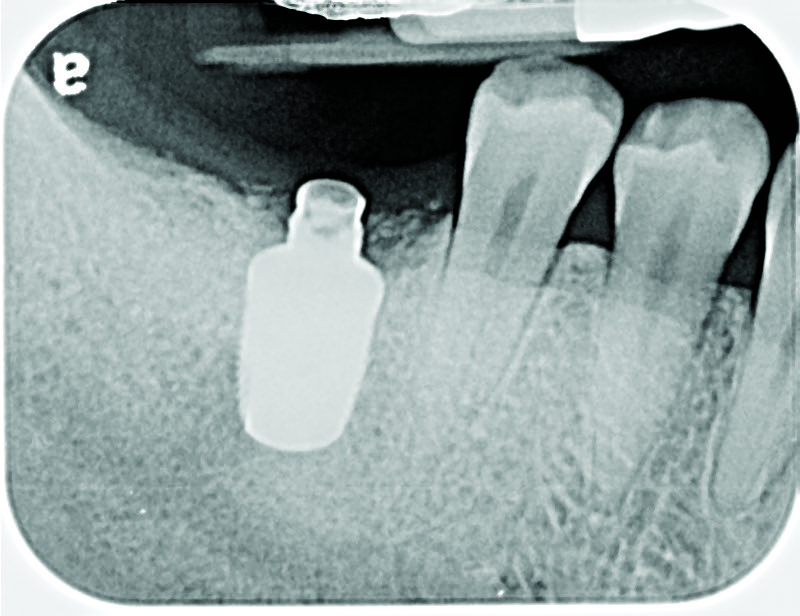

Fig 8. Loss of restoration and subsequent tissue overgrowth from broken abutment screw as shown in the radiograph (Fig 9).

Figure 8

Fig 9. Radiograph depicting fractured screw inside of the implant.

Figure 9